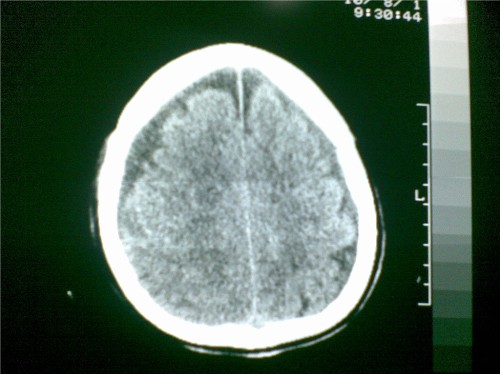

标题: CT28096:男,75岁,外伤10天后,现在恶心、呕吐。是硬膜下积 [打印本页]

标题: CT28096:男,75岁,外伤10天后,现在恶心、呕吐。是硬膜下积

硬膜下积液、右侧基底节、左侧放射冠腔梗。

硬膜下积液、多发性腔梗。

1)双侧额颞顶部硬膜下积液;建议必要时复查。2)多发性腔隙性脑梗塞。